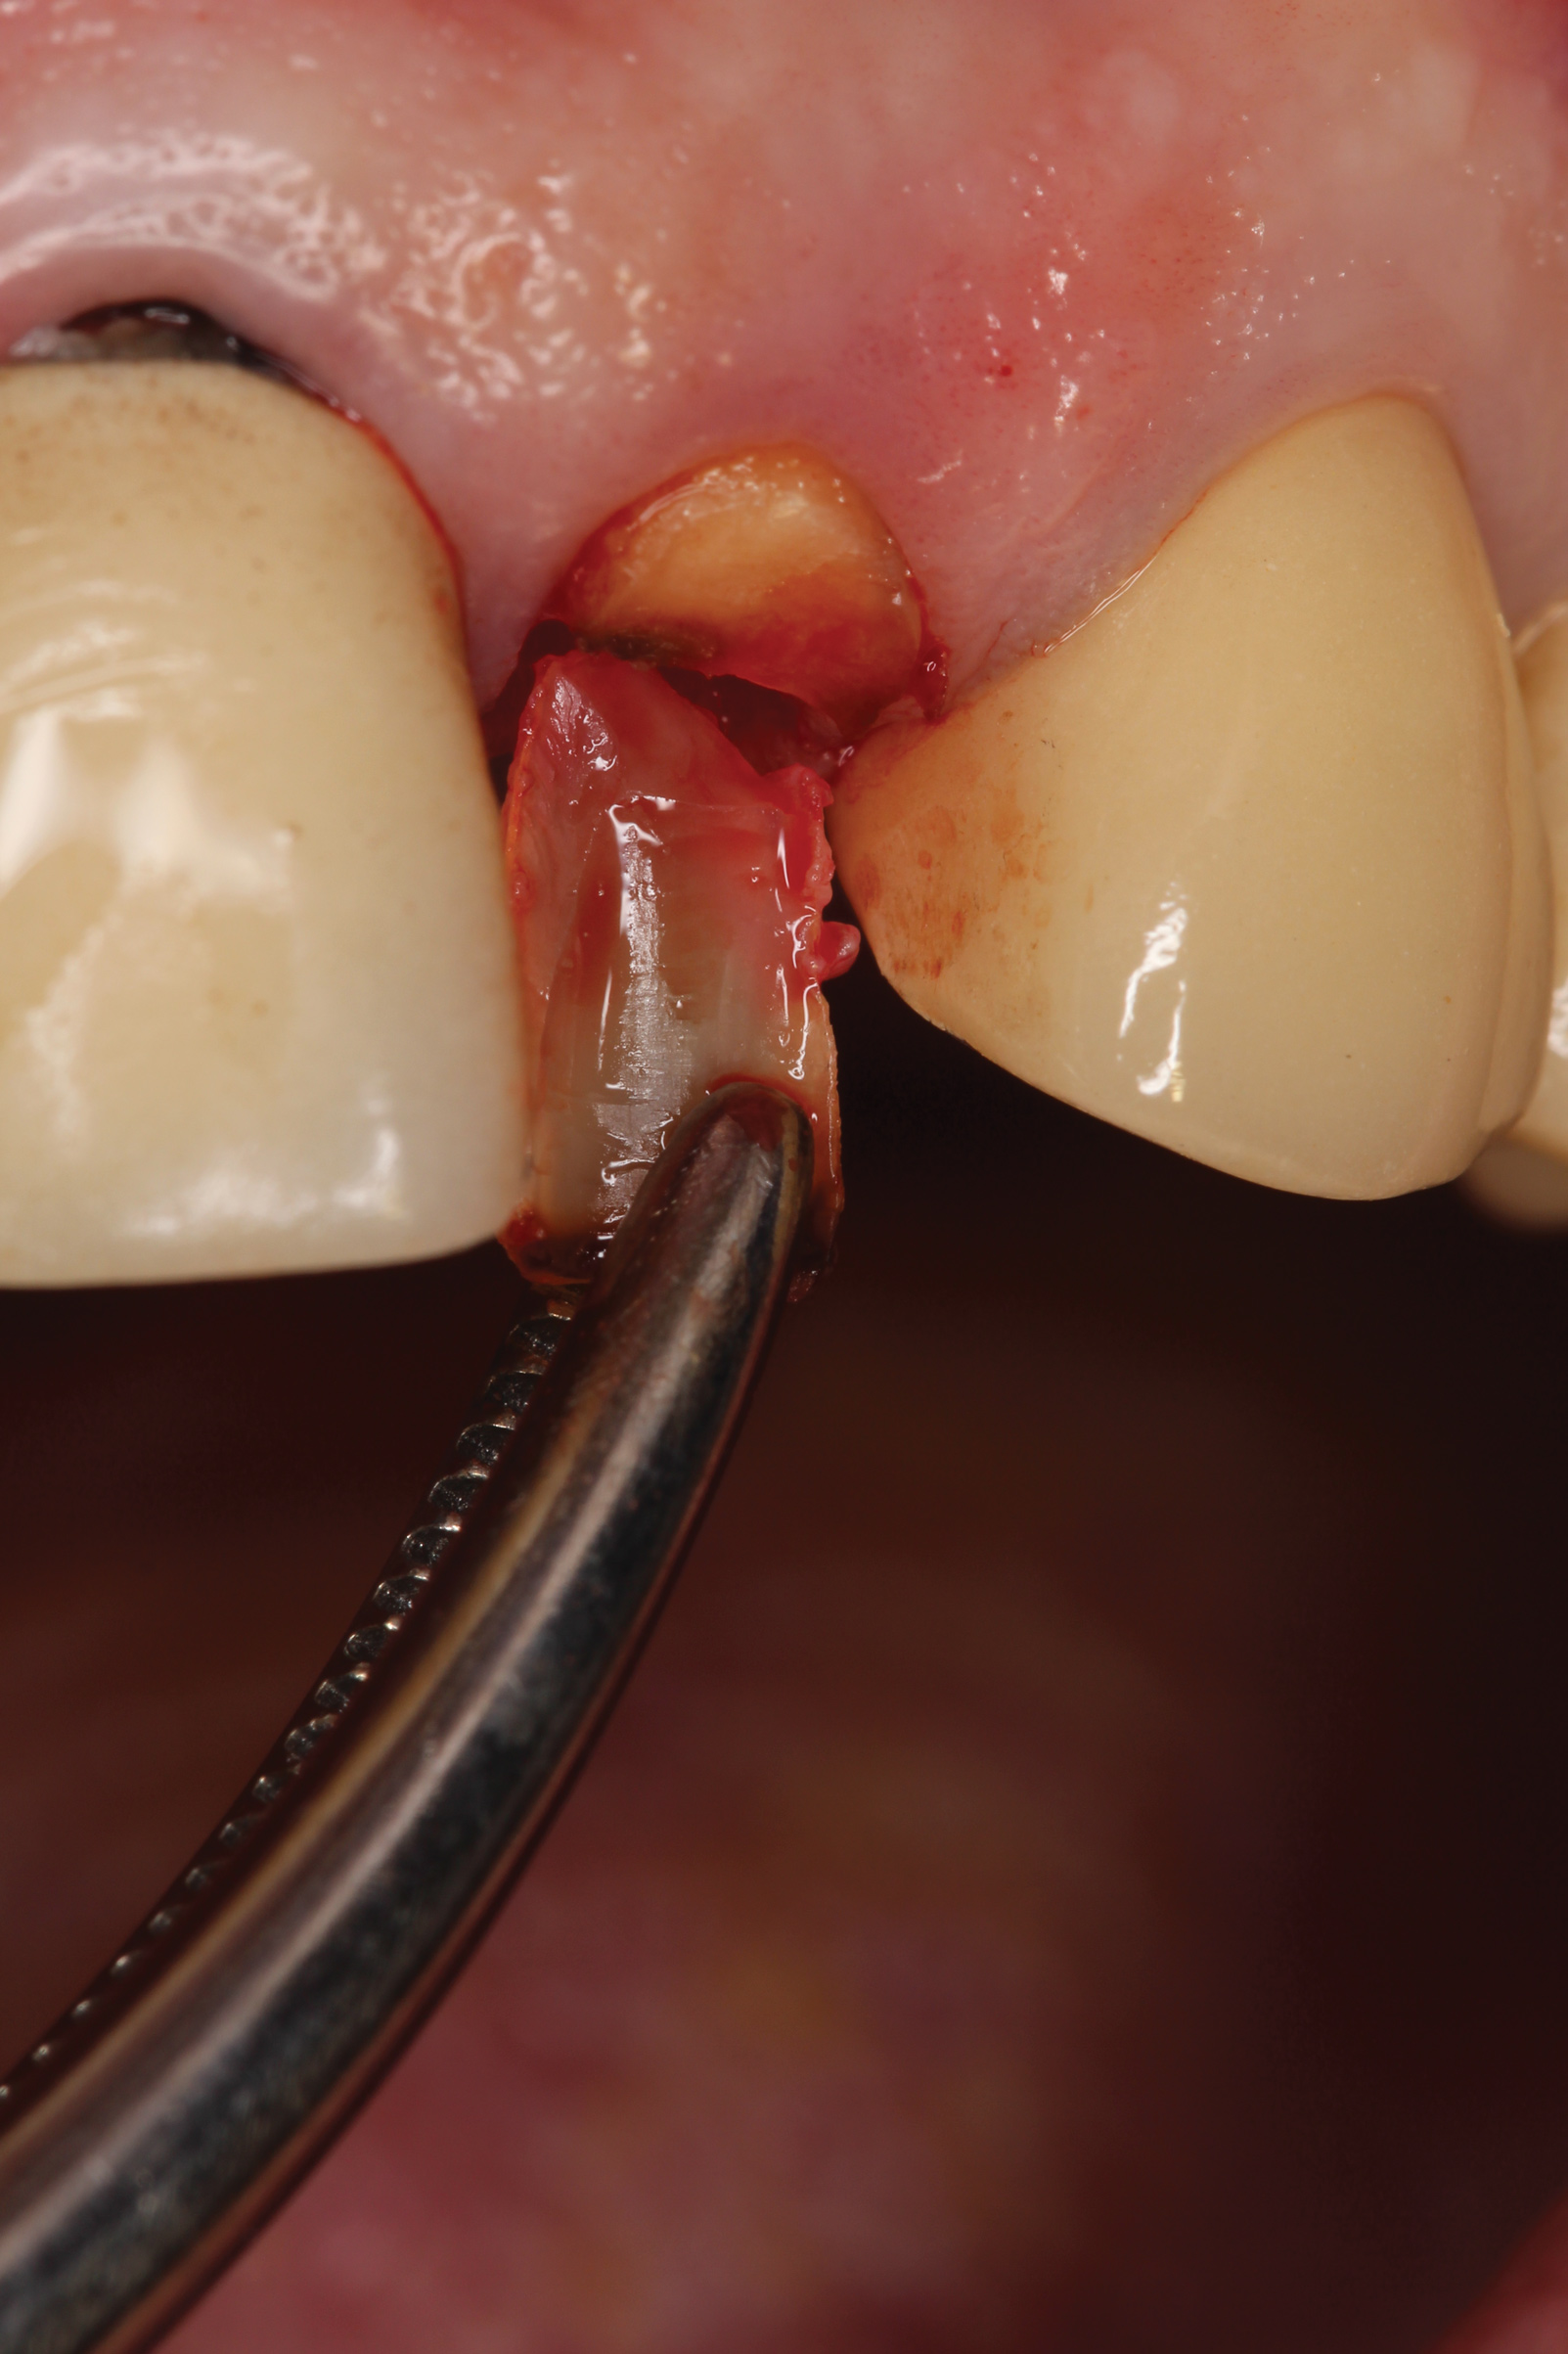

A 65-year-old male patient presented to the office with a fractured maxillary left lateral incisor (Figure 16). Radiographic analysis revealed minimal buccal bone. Having deemed the tooth nonrestorable, the clinician presented several options to the patient, which they carefully reviewed together. A socket-shield approach was selected with the goal of maintaining existing gingival zenith long-term.

Fig 16. Patient presented with fractured maxillary left lateral incisor. Radiographic analysis (not shown) revealed minimal buccal bone. A socket shield was planned during tooth extraction to preserve gingival contours.

Figure 16

Fig 17. The root was sectioned mesial-distal, followed by removal of the palatal root half.

Figure 17

Fig 18. Remaining facial root was contoured to a thickness of 1.5 mm.

Figure 18